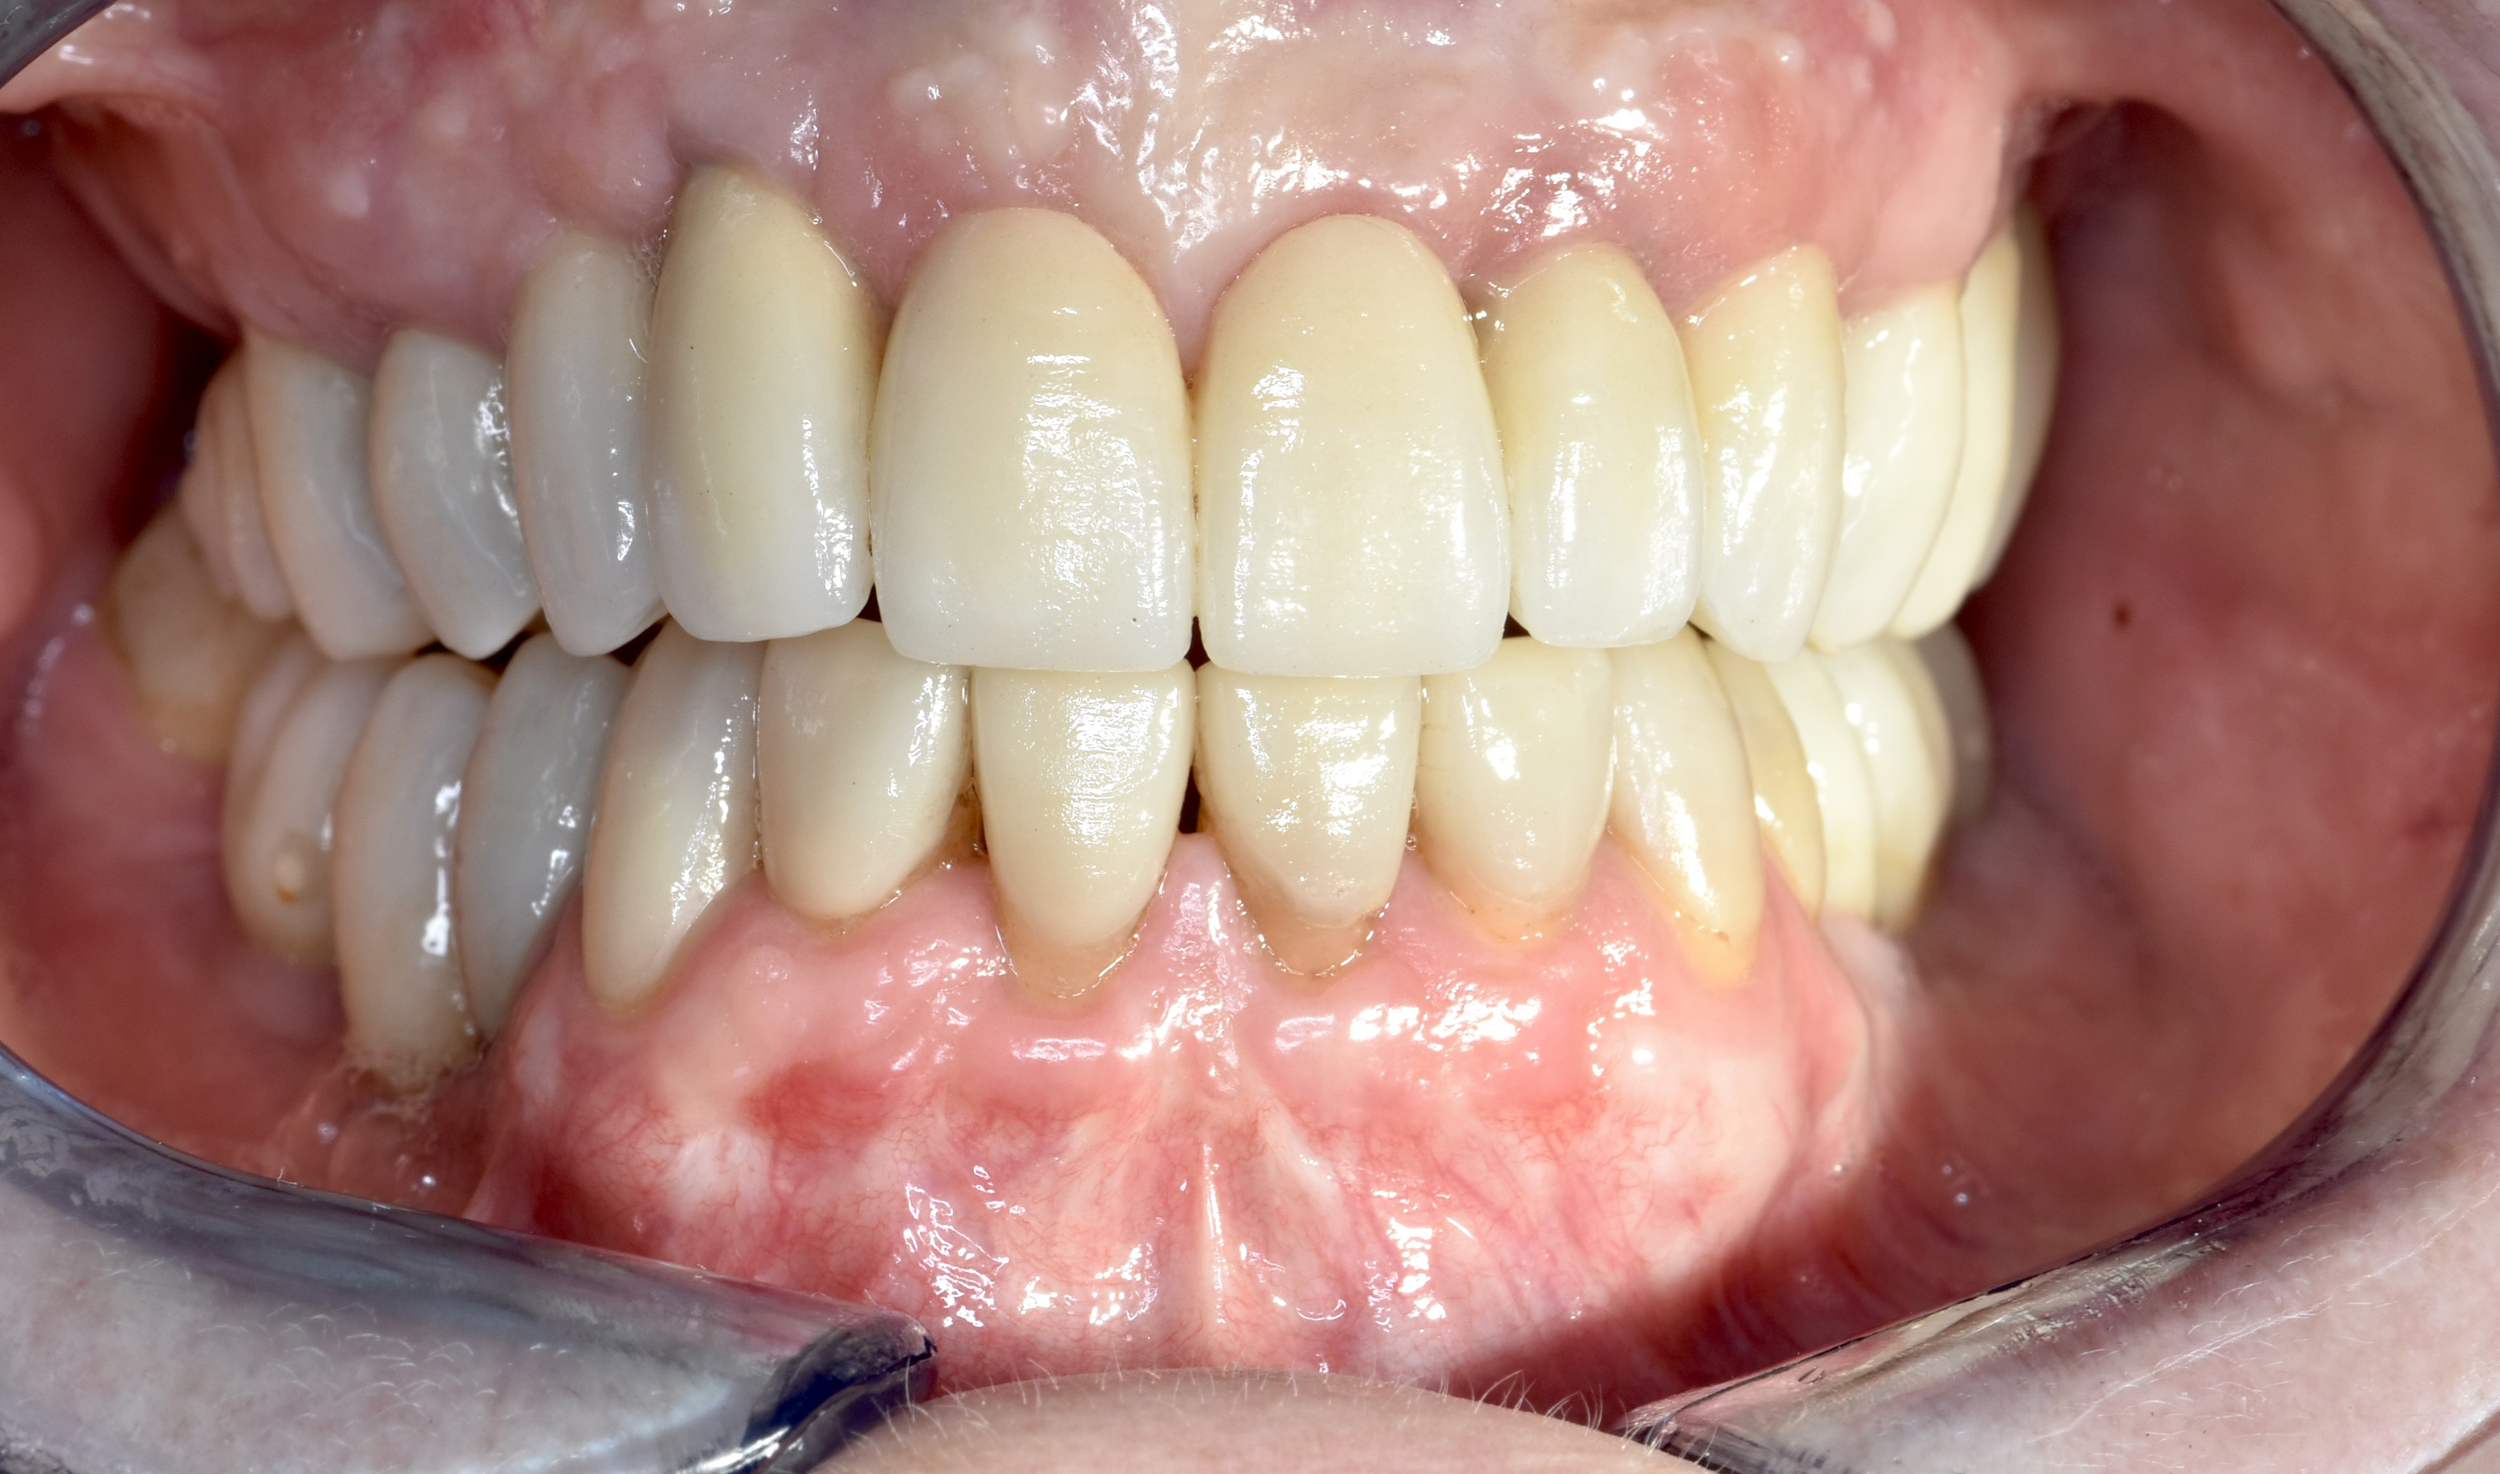

Riabilitazioni complesse con mantenimento

dei denti naturali

In alcune situazioni, anche quando è necessario inserire più impianti, è possibile preservare i denti naturali presenti e valorizzarli con altri trattamenti come ortodonzia, faccette, corone o innesti gengivali. Questo approccio permette di combinare diverse tecniche per ottenere un risultato finale armonioso, funzionale e naturale, rispettando al massimo la struttura dentaria residua.

Caso 3 - Caso 4

DOPO